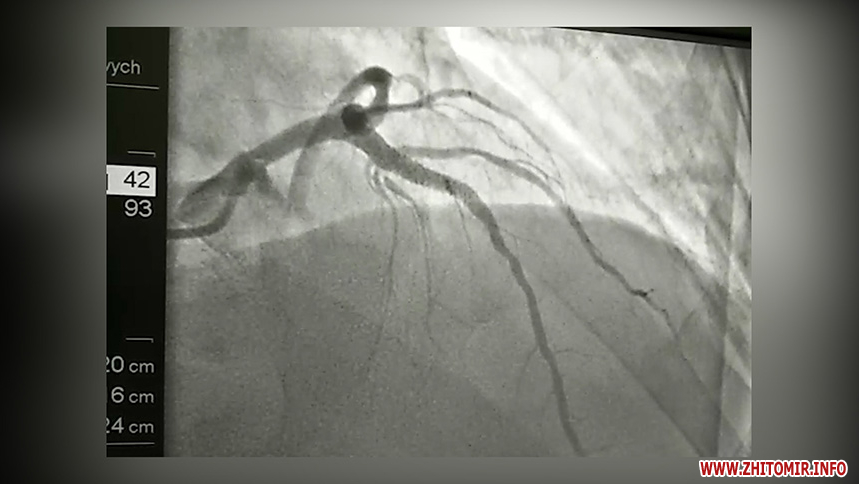

«Такого пацієнта терміново доставляють в операційну, виконується ургентна коронарографія, механічно відкривається судина, імплантується стент, який відновлює кровотік. Відповідно лікування і якість життя пацієнта стає іншим», - зауважує Микола Кушнір.